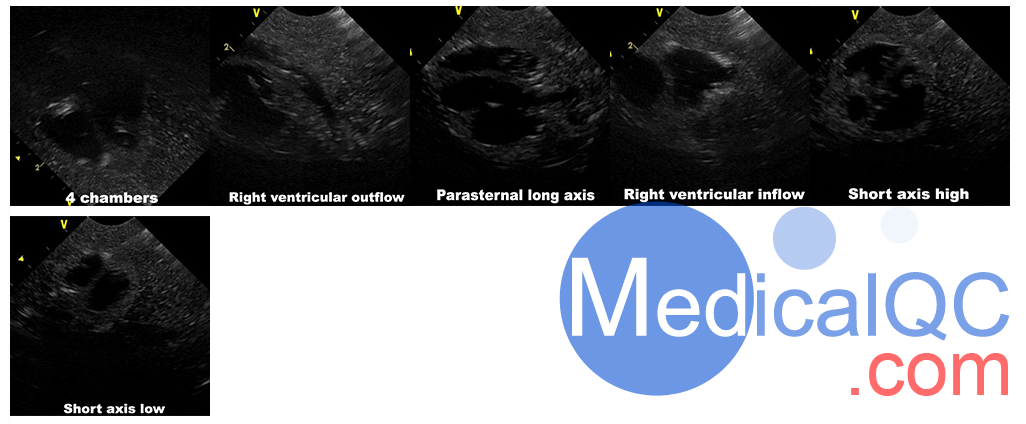

Truephantom US-NO1新生儿躯干超声训练模体,US-NO1新生儿躯干超声模体是基于40周大婴儿的平均新生解剖学设计的,它是由适合超声成像的逼真组织模仿材料制成的。它可用于医学成像和培训目的。Truephantom US-NO1新生儿躯干超声训练模体,US-NO1新生儿躯干超声模体包含以下功能:

心

IVC

肝

它是训练以下内容的工具:

在超声引导下将导管通过脐带插入右心房所需的技能

在超声引导下识别和导出完整且空的膀胱所需的技能